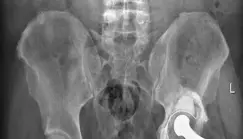

## مقدمة: فهم جراحة مراجعة مفصل الورك الكلي تُعد جراحة استبدال مفصل الورك الكلي (Total Hip Arthroplasty - THA) إحدى أنجح العمليات الجراحية في جراحة العظام، حيث توفر راحة كبيرة من الألم وتحسينًا في الحركة ونوعية الحياة للمرضى الذين يعانون من تلف شديد في مفصل الورك. ومع ذلك، فإن المفاصل الصناعية، مثل أي مكون ميكانيكي، لها عمر افتراضي وقد تحتاج إلى مراجعة أو استبدال بمرور الوقت. تُعرف هذه العملية الثانية باسم "جراحة مراجعة مفصل الورك الكلي" (Revision Total Hip Arthroplasty)، وهي إجراء أكثر تعقيدًا يهدف إلى استبدال المكونات الفاشلة للمفصل الصناعي وتحسين وظيفة الورك وتقليل الألم. إحدى التحديات الرئيسية في جراحات المراجعة هي التعامل مع فقدان العظم الذي يحدث غالبًا نتيجة لتفكك المفصل السابق أو تحلل العظم. هنا يأتي دور التقنيات المتقدمة مثل استخدام "كؤوس التانتالوم المسامية" (Porous Tantalum Cups) ودعاماتها، والتي توفر حلاً مبتكرًا لاستعادة الثبات وتشجيع نمو العظم الجديد. في هذه المقالة الشاملة، سنستكشف بعمق جراحة مراجعة مفصل الورك، مع التركيز على دور كؤوس التانتالوم المسامية في تحقيق الاستقرار الدائم. سنوضح الأسباب التي تستدعي هذه الجراحة، الأعراض، كيفية التشخيص، خيارات العلاج المتاحة، وخطوات التعافي. كما سنسلط الضوء على الخبرة الرائدة للأستاذ الدكتور محمد هطيف في صنعاء، والذي يُعد من أبرز الجراحين المتخصصين في جراحات مراجعة مفصل الورك المعقدة، ويوفر للمرضى أحدث التقنيات وأفضل النتائج.  ## تشريح مفصل الورك وفهم المفصل الصناعي لفهم جراحة مراجعة مفصل الورك، من الضروري أولاً فهم التشريح الطبيعي للمفصل وكيف يعمل المفصل الصناعي. ### التشريح الطبيعي لمفصل الورك مفصل الورك هو مفصل كروي حُقي كبير يربط عظم الفخذ (الفخذ) بالحوض. يتكون من: * **رأس عظم الفخذ:** الجزء العلوي الكروي لعظم الفخذ. * **الحُق (Acetabulum):** تجويف على شكل كوب في عظم الحوض يستقبل رأس عظم الفخذ. * **الغضروف المفصلي:** نسيج ناعم يغطي أسطح العظام داخل المفصل، مما يسمح بحركة سلسة وغير مؤلمة. هذا التركيب يسمح بحركة واسعة النطاق للورك، مما يتيح لنا المشي والجري والانحناء. ### مكونات مفصل الورك الصناعي عندما يتلف مفصل الورك الطبيعي بسبب التهاب المفاصل الشديد أو الإصابة، يتم استبداله بمفصل صناعي يتكون عادة من أربعة أجزاء رئيسية: * **الساق الفخذية (Femoral Stem):** جزء معدني يُدخل في تجويف عظم الفخذ. * **الرأس الفخذي (Femoral Head):** كرة معدنية أو خزفية تُثبت على الجزء العلوي من الساق الفخذية، وتعمل كبديل لرأس عظم الفخذ الطبيعي. * **الكأس الحُقي (Acetabular Cup):** غلاف معدني على شكل كوب يُزرع في تجويف الحُق في الحوض. * **البطانة (Liner):** بطانة مصنوعة من البولي إيثيلين (البلاستيك)، أو السيراميك، أو المعدن، تُوضع داخل الكأس الحُقي لتوفير سطح أملس للرأس الفخذي للتحرك عليه. تعمل هذه المكونات معًا لتقليد وظيفة مفصل الورك الطبيعي، مما يتيح للمريض استعادة الحركة وتقليل الألم.  ## الأسباب وعوامل الخطر التي تستدعي مراجعة مفصل الورك على الرغم من أن مفصل الورك الصناعي يمكن أن يدوم لسنوات عديدة، إلا أن هناك عدة أسباب قد تؤدي إلى فشله وتتطلب جراحة مراجعة. فهم هذه الأسباب أمر بالغ الأهمية للمرضى والأطباء على حد سواء. ### الأسباب الشائعة لفشل مفصل الورك الصناعي * **التفكك اللاجرثومي (Aseptic Loosening):** هذا هو السبب الأكثر شيوعًا لمراجعة مفصل الورك. يحدث عندما يفقد المفصل الصناعي ارتباطه بالعظم المحيط دون وجود عدوى. يمكن أن يكون بسبب التآكل الميكانيكي أو تفاعل الجسم مع جزيئات التآكل الصغيرة. * **تحلل العظم (Osteolysis):** غالبًا ما يرتبط بالتفكك اللاجرثومي. تحدث هذه الحالة عندما تتآكل جزيئات صغيرة من البطانة البلاستيكية (البولي إيثيلين) أو المعدن أو السيراميك، ويقوم الجهاز المناعي للجسم بالاستجابة لهذه الجزيئات عن طريق امتصاص العظم المحيط بالمفصل الصناعي. هذا يؤدي إلى تكوين فراغات أو عيوب في العظم، مما يضعف تثبيت المفصل. * **تآكل البطانة (Liner Wear):** بمرور الوقت، يمكن أن تتآكل البطانة البلاستيكية داخل الكأس الحُقي، مما يؤدي إلى زيادة الاحتكاك، وتوليد جزيئات تآكل، وفقدان الثبات. * **العدوى (Infection):** على الرغم من ندرتها، يمكن أن تحدث العدوى حول المفصل الصناعي. قد تكون حادة (تظهر بعد وقت قصير من الجراحة) أو مزمنة (تتطور ببطء على مدى أشهر أو سنوات). تتطلب العدوى عادةً إزالة المفصل الصناعي وتنظيف المنطقة ووضع مفصل جديد بعد علاج العدوى. * **عدم الاستقرار أو الخلع المتكرر (Instability or Recurrent Dislocation):** قد يخرج رأس المفصل الصناعي من الكأس الحُقي (خلع) بشكل متكرر، مما يسبب ألمًا شديدًا ويحد من الحركة. قد يكون هذا بسبب وضع غير صحيح للمكونات، أو ضعف الأنسجة الرخوة، أو صدمة. * **الكسر حول المفصل (Periprosthetic Fracture):** قد يحدث كسر في العظم المحيط بالمفصل الصناعي نتيجة لسقوط أو إصابة، مما يتطلب جراحة مراجعة لإصلاح الكسر وتثبيت المفصل. * **الألم المستمر (Persistent Pain):** في بعض الحالات، قد يستمر الألم بعد جراحة استبدال المفصل الكلي الأول، حتى لو لم يكن هناك تفكك واضح أو عدوى. ### حالة المريض المذكورة في الحالة التي نتناولها، كان المريض يعاني من **تحلل العظم والفشل الميكانيكي** لمفصل الورك الكلي، وهي أسباب شائعة تستدعي المراجعة. كان المفصل الصناعي السابق مثبتًا بالأسمنت، مما أضاف تعقيدًا لعملية الإزالة.  ## الأعراض والعلامات التي تشير إلى الحاجة لمراجعة مفصل الورك عندما يفشل مفصل الورك الصناعي، غالبًا ما تظهر مجموعة من الأعراض التي تدفع المريض لطلب المساعدة الطبية. من المهم التعرف على هذه العلامات مبكرًا لضمان التدخل في الوقت المناسب. ### الأعراض الشائعة لفشل المفصل الصناعي * **الألم:** هذا هو العرض الأكثر شيوعًا. قد يكون الألم: * **مرتبطًا بالنشاط:** يزداد مع الحركة أو الوقوف أو المشي. * **ألم ليلي:** يوقظ المريض من النوم. * **ألم في الورك أو الفخذ العلوي:** غالبًا ما يتركز في هذه المناطق، وقد يمتد إلى الأربية أو الركبة. * **عدم الاستقرار أو "الشعور بالخلع":** قد يشعر المريض أن المفصل على وشك الخروج من مكانه، أو قد يتعرض لخلع فعلي. * **العرج (Limp):** تغير في طريقة المشي بسبب الألم أو عدم الثبات أو اختلاف طول الساقين. * **تصلب المفصل أو انخفاض نطاق الحركة:** قد يصبح من الصعب تحريك الورك بحرية كما كان من قبل. * **اختلاف طول الساقين (Limb Length Discrepancy):** قد تصبح الساق التي بها المفصل الصناعي أقصر أو أطول من الساق الأخرى، مما يؤثر على المشي ويسبب آلامًا في الظهر أو الورك. * **صوت طقطقة أو احتكاك:** قد يسمع المريض أو يشعر بضوضاء غير طبيعية من المفصل. * **التورم أو الاحمرار أو السخونة:** في حالة وجود عدوى، قد تظهر هذه العلامات حول المفصل. ### الأعراض في حالة المريض في حالة المريض الذي نناقشه، كانت الأعراض الرئيسية كالتالي: * **ألم في الورك الأيسر مرتبط بالنشاط:** استمر لمدة عام تقريبًا، مما يشير إلى مشكلة مزمنة. * **ألم ليلي:** دليل على تفاقم المشكلة حتى في فترات الراحة. * **اختلاف طول الساقين:** كانت الساق اليسرى أقصر بمقدار 2 بوصة من الساق اليمنى، مما يؤثر بشكل كبير على المشي والتوازن. * **مشية عرجاء (Antalgic gait):** مشية مميزة يحاول فيها المريض تقليل الوزن على الساق المؤلمة. * **انخفاض نطاق الحركة:** تحديدًا، انخفاض في الدوران الداخلي للورك. * **عدم وجود شكوى من عدم الاستقرار:** على الرغم من وجود مشكلة، لم يبلغ المريض عن شعور بالخلع، مما قد يوجه التشخيص بعيدًا عن مشاكل عدم الثبات الأولية. هذه الأعراض مجتمعة تشير بوضوح إلى فشل المفصل الصناعي السابق وتتطلب تقييمًا طبيًا عاجلاً.  ## التشخيص الدقيق: خطوات نحو العلاج الصحيح يتطلب التشخيص الدقيق لفشل مفصل الورك الصناعي تقييمًا شاملاً يجمع بين الفحص السريري، والتقييم الإشعاعي، وأحيانًا الفحوصات المخبرية. يمتلك الأستاذ الدكتور محمد هطيف في صنعاء الخبرة اللازمة لتوجيه هذه العملية التشخيصية المعقدة. ### 1. التاريخ المرضي والفحص السريري * **التاريخ المرضي:** يبدأ الطبيب بسؤال المريض عن تاريخه الطبي الكامل، بما في ذلك الجراحة السابقة لمفصل الورك، والأعراض الحالية (متى بدأت، شدتها، العوامل التي تزيدها أو تقللها)، وأي أمراض مزمنة أو أدوية يتناولها. في حالة المريض، كان تاريخه يتضمن تحلل العظم والفشل الميكانيكي، وهو مدخن سابق، ويعاني من السمنة. * **الفحص السريري:** يقوم الأستاذ الدكتور محمد هطيف بإجراء فحص دقيق للورك والساقين، ويشمل ذلك: * **ملاحظة المشية:** تقييم العرج وأي أنماط مشي غير طبيعية. * **تقييم نطاق الحركة:** قياس مدى قدرة المريض على تحريك وركه في اتجاهات مختلفة (الثني، الدوران الداخلي والخارجي). * **اختبارات محددة:** مثل تقييم فرق طول الساقين، وفحص الأعصاب والأوعية الدموية للتأكد من سلامتها. في حالة المريض، لوحظ فرق في طول الساقين بمقدار 2 بوصة، وسلامة النبضات البعيدة والفحص الحسي الحركي. ### 2. التقييم الإشعاعي والتصوير يُعد التصوير الإشعاعي حجر الزاوية في تشخيص فشل مفصل الورك الصناعي.